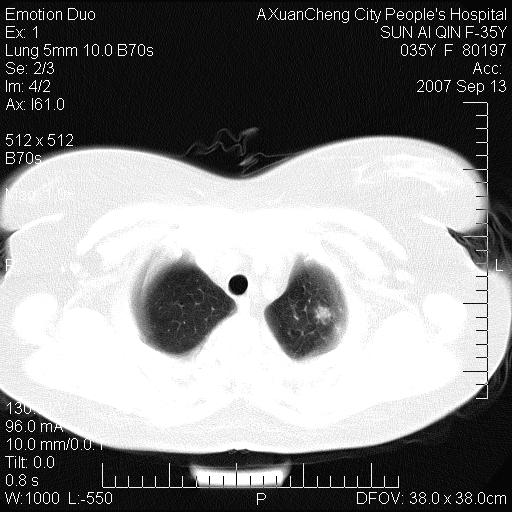

以下是引用天南地北在2007-9-13 13:43:00的发言:[br]考虑双肺、肺门侵润

以下是引用ydx_74在2007-9-13 15:42:00的发言:[br]仅看片,考虑右上肺癌并双肺转移,结合病史,考虑肺门、肺内淋巴侵润

以下是引用同在2007-9-13 15:08:00的发言:[br]支持肺门及双肺侵润.